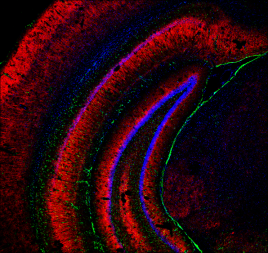

“In questo nuovo lavoro abbiamo dimostrato che nel cervello, durante le prime fasi della malattia di Alzheimer, le alterazioni tipiche dell’insulino-resistenza cerebrale determinano un aumento della quantità dell’enzima zDHHC7 e l’alterata S-palmitoilazione di proteine importanti per la regolazione delle funzioni cognitive e dell’accumulo di proteina beta-amiloide”, dice Fusco.

“I nostri dati dimostrano che, in modelli sperimentali di Alzheimer, l’inibizione sia farmacologica sia genetica della S-palmitoilazione proteica sia in grado di contrastare l’accumulo di proteine dannose per i neuroni e ritardare l’insorgenza e la progressione del declino cognitivo. Inoltre, anche nei cervelli post-mortem di pazienti deceduti con l’Alzheimer abbiamo riscontrato elevati livelli di zDHHC7 e di S-palmitoilazione proteica, identificando una correlazione inversa tra i livelli di S-palmitoilazione della proteina BACE1 e il mantenimento delle funzioni cognitive nei pazienti”, aggiunge Francesca Natale, primo autore dello studio. In pratica i pazienti con bassi livelli di S-palmitoilazione della proteina BACE1 totalizzavano punteggi migliori alla scala di valutazione cognitiva in uso, la Mini Mental State Examination (MMSE).

Quando in esperimenti condotti su topi geneticamente modificati che riproducono il quadro clinico della malattia di Alzheimer i ricercatori hanno spento gli enzimi zDHHC con un farmaco sperimentale somministrato tramite spray nasale, il “2-bromopalmitato”, sono riusciti a fermare la neurodegenerazione e frenato i sintomi tipici, riducendo, tra l’altro, l’accumulo di beta-amiloide e da ultimo allungando la vita degli animali.